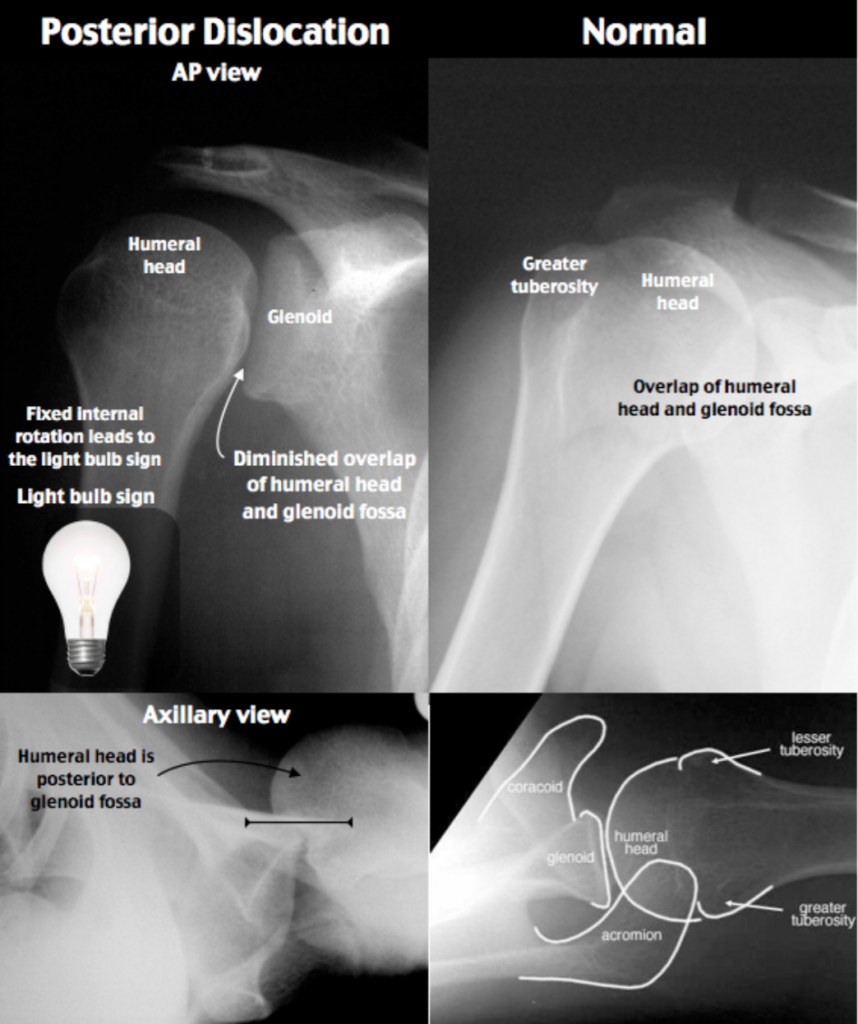

Doc Cottle's Desk Posterior shoulder dislocation confirmed by ultrasound

Posterior Shoulder Dislocation EMbeds.co.uk Signs Of Dislocation Shoulder Common symptoms of a dislocated shoulder. Shoulder dislocation (correctly termed a glenohumeral joint dislocation) involves separation of the humerus from the glenoid of the scapula at the glenohumeral joint. Dislocating your shoulder can cause immediate and intense symptoms. Because the shoulder is only partially dislocated, the bones can move back into place (relocate) on their own, and the joint may.. Signs Of Dislocation Shoulder.

Posterior Shoulder Dislocation EMbeds.co.uk Signs Of Dislocation Shoulder A partial shoulder dislocation, or subluxation, can be harder to detect. Shoulder dislocation (correctly termed a glenohumeral joint dislocation) involves separation of the humerus from the glenoid of the scapula at the glenohumeral joint. Symptoms of a dislocated shoulder. Learn more about their symptoms, and. The shoulder is the most mobile joint in the body but also. What are dislocated. Signs Of Dislocation Shoulder.

Posterior Shoulder Dislocation • LITFL • Trauma Library Signs Of Dislocation Shoulder The most common symptoms of a dislocated shoulder include: The shoulder is the most mobile joint in the body but also. md explains the difference between a dislocated shoulder and a separated shoulder. An unexplained pain in your shoulder can mean many things, including. Shoulder dislocation (correctly termed a glenohumeral joint dislocation) involves separation of the humerus from the glenoid. Signs Of Dislocation Shoulder.

Posterior Shoulder Dislocation • LITFL • Trauma Library Signs Of Dislocation Shoulder Shoulder dislocation (correctly termed a glenohumeral joint dislocation) involves separation of the humerus from the glenoid of the scapula at the glenohumeral joint. An unexplained pain in your shoulder can mean many things, including. Common symptoms of a dislocated shoulder. What are dislocated shoulder symptoms? The most common symptoms of a dislocated shoulder include: Symptoms of a dislocated shoulder. md. Signs Of Dislocation Shoulder.